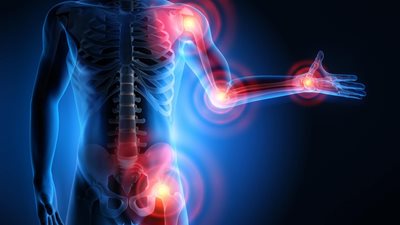

تحدث الدكتور أحمد إبراهيم صالح، مدرس جراحة العظام بكلية طب جامعة المنصورة، عن كسر العظمة الزورقية، موضحًا أن عظمة الزورقية واحدة من 8 عظمات في المعصم ومسئولة بنسبة 80 % عن تحويل الحمل من الذراع إلى اليد، وبالتالي هي المسئولة عن نقل قوة الذراع من أعلى إلى أسفل.

أما عن الأعراض التي تظهر حال كسر العظمة الزروقية، أشار الدكتور أحمد إبراهيم، إلى أن حال إنكسار العظمة يلاحظ المريض تورم في اليد وآلم شديد في منطقة المعصم، بالإضافة إلى أن في بعض الحالات قد يشعر المريض بعدم القدرة على تحريك إصبع الأبهام.